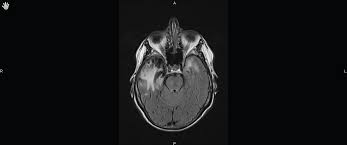

Brain Mri Scans Of A Patient With Acute Herpes Simplex Type 1 Download Scientific Diagram

Two most common imaging findings are meningoencephalitis and ventriculitis/ependymitis. Lumbar puncture showing isolated mild pleocytosis. Mri is the preferred imaging modality for hsv encephalitis. The clinical syndrome is often characterized by the rapid onset. Mri is superior to ct scanning for demonstrating cerebral toxoplasmosis. Encephalitis in the immunocompromised host. Due to lack of facilities. Herpes simplex encephalitis is a type of infectious encephalitis which happens when herpes simplex virus (hsv) enters the brain. Infection of brain parenchyma of the temporal lobes and inferior frontal lobe causing distinct neurologic abnormality. Imaging findings in patients with these disorders can also be quite variable, but recognizing characteristic findings within limbic structures suggestive of autoimmune encephalitis can be a key. Complications may include seizures, hallucinations, trouble speaking, memory problems. Encephalitis is an infectious or inflammatory disorder of the brain manifest by fever and headache and associated with a depressed level of consciousness, an altered mental status (confusion, behavioral. Encephalitis • usually hsv1 (hsv 2:

• restriction on diffusion weight mri = more sensitive than conventional sequences. Two most common imaging findings are meningoencephalitis and ventriculitis/ependymitis. Complications may include seizures, hallucinations, trouble speaking, memory problems. Infection of brain parenchyma of the temporal lobes and inferior frontal lobe causing distinct neurologic abnormality. Herpes simplex encephalitis (hse) is a rare neurological disorder characterized by inflammation of the brain (encephalitis).